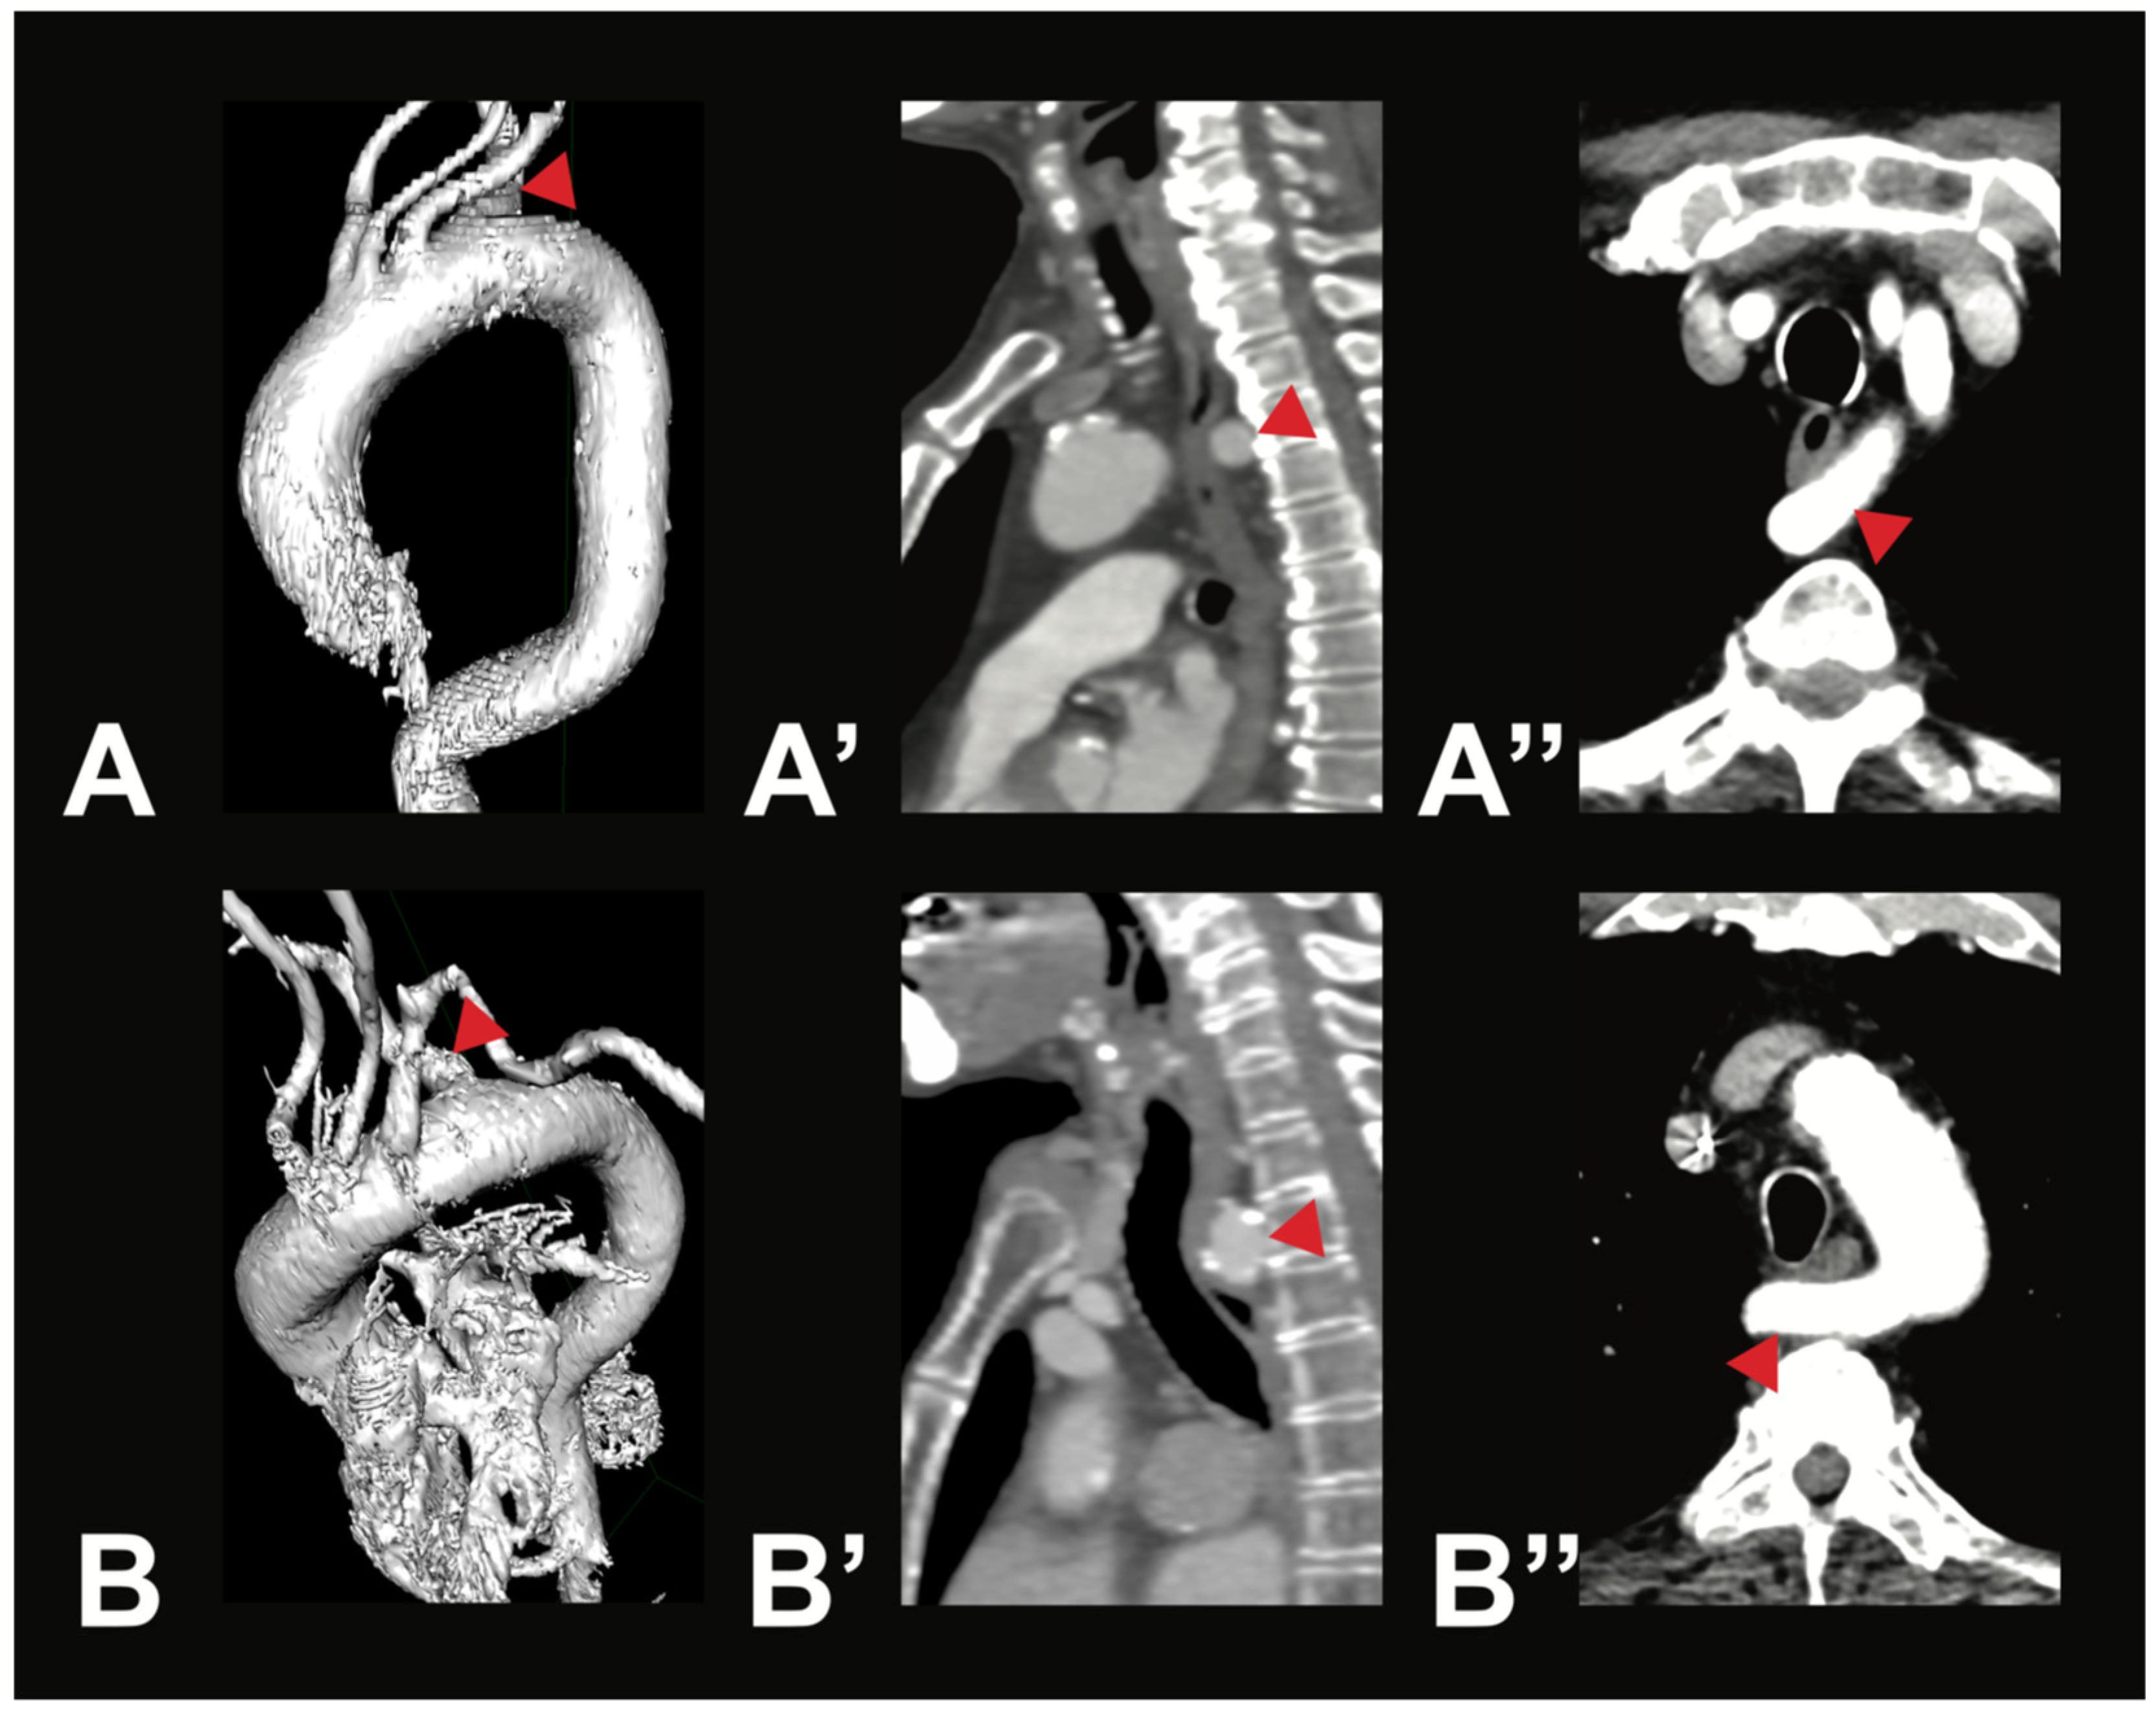

Figure 3.

Most symptomatic AA variations—arteria lusoria. Depicted are two exemplary cases of arteria lusoria (V5) in a 71-year-old male patient (A—3D reconstruction, A’—sagittal view, A’’—axial view) and a 79-year-old female patient (B—3D reconstruction, B’—sagittal view, B’’—axial view). In both cases, the RSA (red arrow) was the last branch of the AA, originating from its left side and running posterior to the esophagus to the right side.

Variant V2i was very uncommon, with only one case identified within the examined population. In this variant, the BCT is absent; instead, the RSA and the RCCA arise directly from the AA. Variant V3b was also rare. It is characterized by three AA branches: first, the BCT, which gives rise to the RSA, the LCCA, and the RCCA; second, the LVA; and third, the LSA. Aortic arch branching variations in groups V4–V8 are extremely uncommon, and in some cases, no instances were identified in any of the 400 analyzed CTAs. However, two rare variations were observed in the study population. In two male individuals (0.5%), the thyroidea ima artery was found originating from the AA (V4). Additionally, a variation in which the right subclavian artery arose directly from the AA (V5) was found in two female individuals (0.5%). In both cases, the RSA followed a retroesophageal course (see Figure 3).

Rarer variations, such as the IMA given off as a direct branch (V4) or the arteria lusoria (V5), were each found in only 0.5% of cases. These values are comparable to previous literature, with V5 reported in under 1% of cases [18,19] and V4 with a prevalence of 0.09% described by Murray [1]. It is important to know that the arteria lusoria can become symptomatic, causing dysphagia lusoria, among other things, through compression of the esophagus [23].